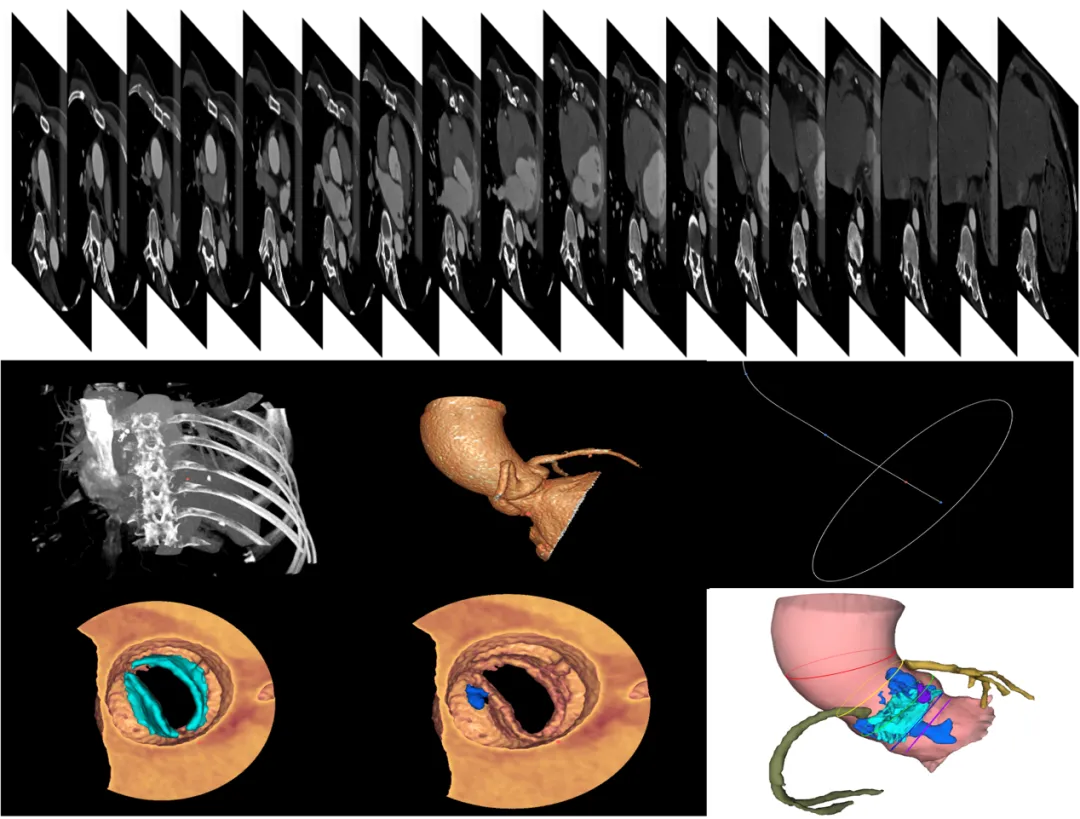

·基于人工智能的TAVR术前评估:通过导入高质量CTA影像至分析系统,自动完成主动脉根部多目标精细分割与3D重建,自动识别瓣叶分型、窦底及冠状动脉开口,精确定位关键解剖结构并测量,同时动态评估钙化斑块,辅助术者精准规划手术方案,提升手术成功率。

·基于人工智能 TAVR术后评估:通过对瓣膜支架的高精度分割、去伪影操作和逐层的全自动形态学指标定量评估,能够精准评价支架膨胀程度和效果,为复盘手术过程、优化手术策略、改进器械设计提供重要参考依据。